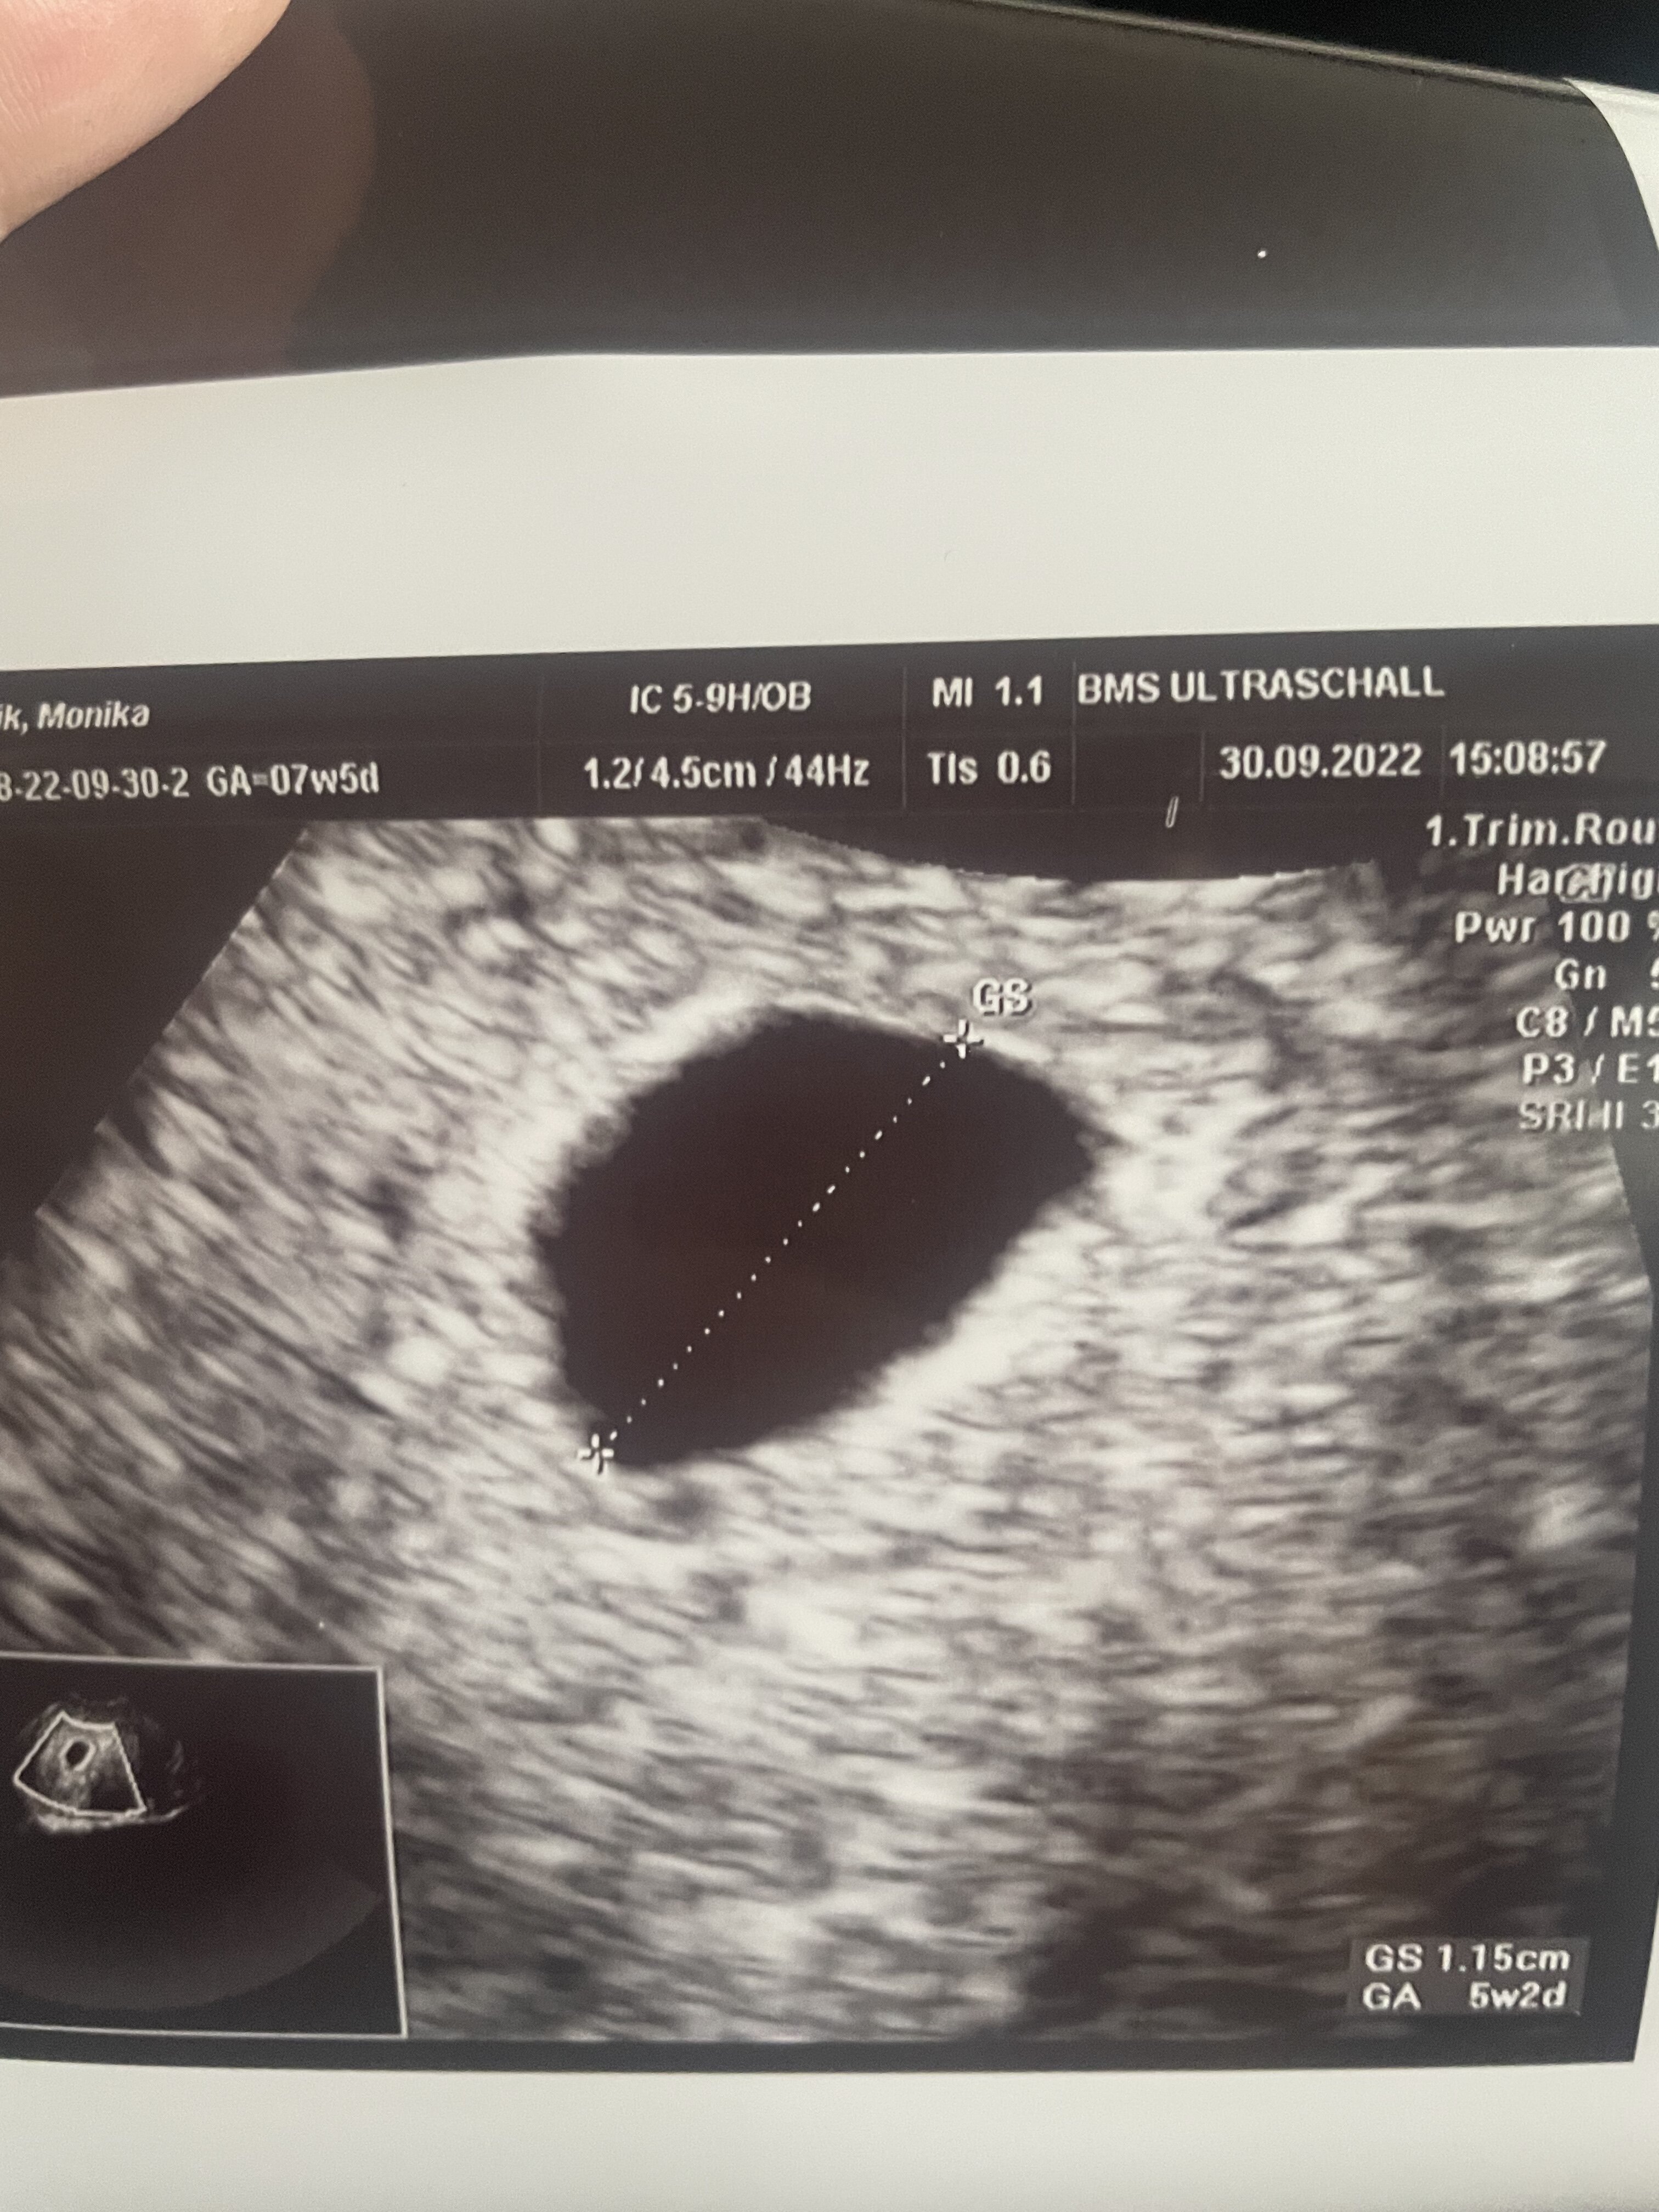

Oczywiście w stresach ( przy plamieniach ) czekając na kolejna wizyte powtórzyłam prywatnie badanie wczoraj, według OM 7w5d według USG 5w2d puste jajo 1.15m ( drugie zdjęcie) kolejne badanie dopiero 8/10 mam padaczkę normalnie. Plamienia nie ustępują ale nie krwawię. Czy po 5 dniach powinno pokazać się żółtaczko? Mega pani doctor ( za która zapłaciłam £150) machała to różdżka pod każdym katem nie ma żółtaczka :( myślicie ze pokaże się coś za tydzień ?